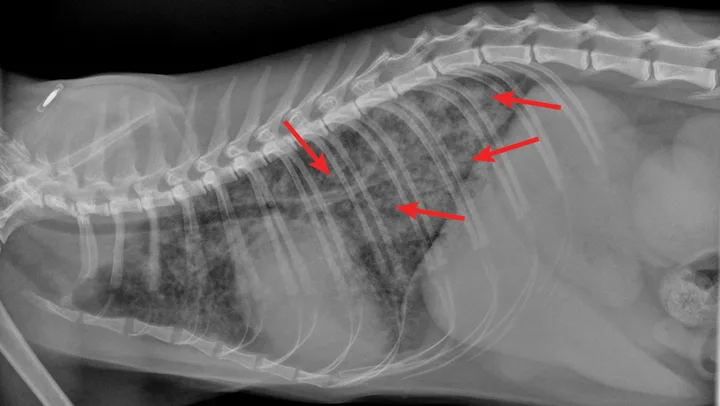

Radiographic evaluation is variable. Classic cranioventral distribution is less common in cats (Figure 3). A bronchial pattern is most common; however, bronchointerstitial, alveolar, and more structured pseudonodular patterns can occur.6,8 Occasionally, pulmonary abscesses may be appreciated and resemble pulmonary neoplasia (Figure 4).

FIGURE 3

Radiograph of bronchopneumonia with more classic cranioventral distribution (arrows). Other diseases, including CHF, have a similar distribution. Lack of this pattern does not rule out infection.